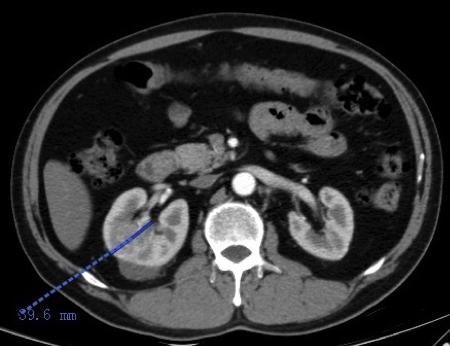

2016.10.26复查肾脏CT:右肾MT较前缩小,肾包膜下少量积液(穿刺后改变),肝内血管瘤,肝小囊肿同前。

(治疗1月缩小到40mm)

2016.11.23再次复查肾脏CT:右肾MT较前进一步缩小,肝内血管瘤,肝小囊肿同前。

治疗2月缩小到33mm

右肾肿瘤最大径缩短从59mm缩小到33mm,缩小达44%,疗效评价PR。